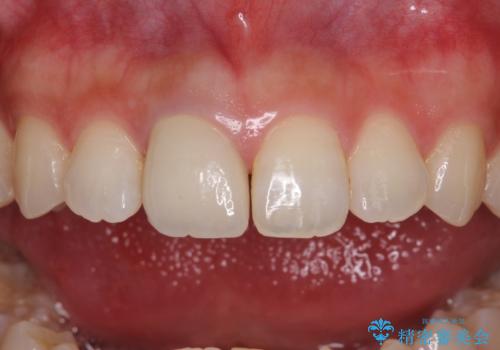

- 近医にて被せた前歯のクラウンの色の違いを気にして来院された患者様です。

オーダーメイドのオールセラミッククラウンにて補綴することとしました。

元々すきっ歯であったため、隙間を全て埋めると左右で大きさがアンバランスとなることが懸念されました。

違和感のない程度に隙間を小さくして、自然な見た目に仕上げました。